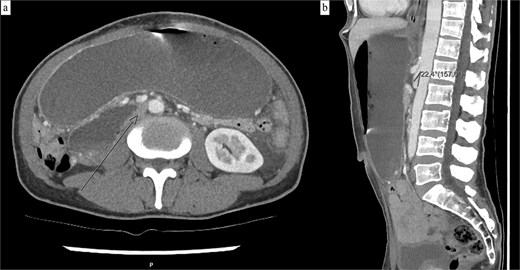

Abdominal computed tomography (CT) showed marked dilation of the stomach, first and second duodenal segments, with abrupt collapse at the retroperitoneal junction between the second and third duodenal segments. The aorto-mesenteric angle was reduced at 22° (Fig. 1), and no intraluminal cause of obstruction was visualized. The CT report subsequently concluded the duodenal obstruction was caused by SMA syndrome.

(a) Axial CT demonstrating a grossly distended stomach, first and second duodenal segments with collapse at the third segment between the abdominal aorta and SMA. (b) Sagittal CT with a measured aorto-mesenteric angle of 22°.